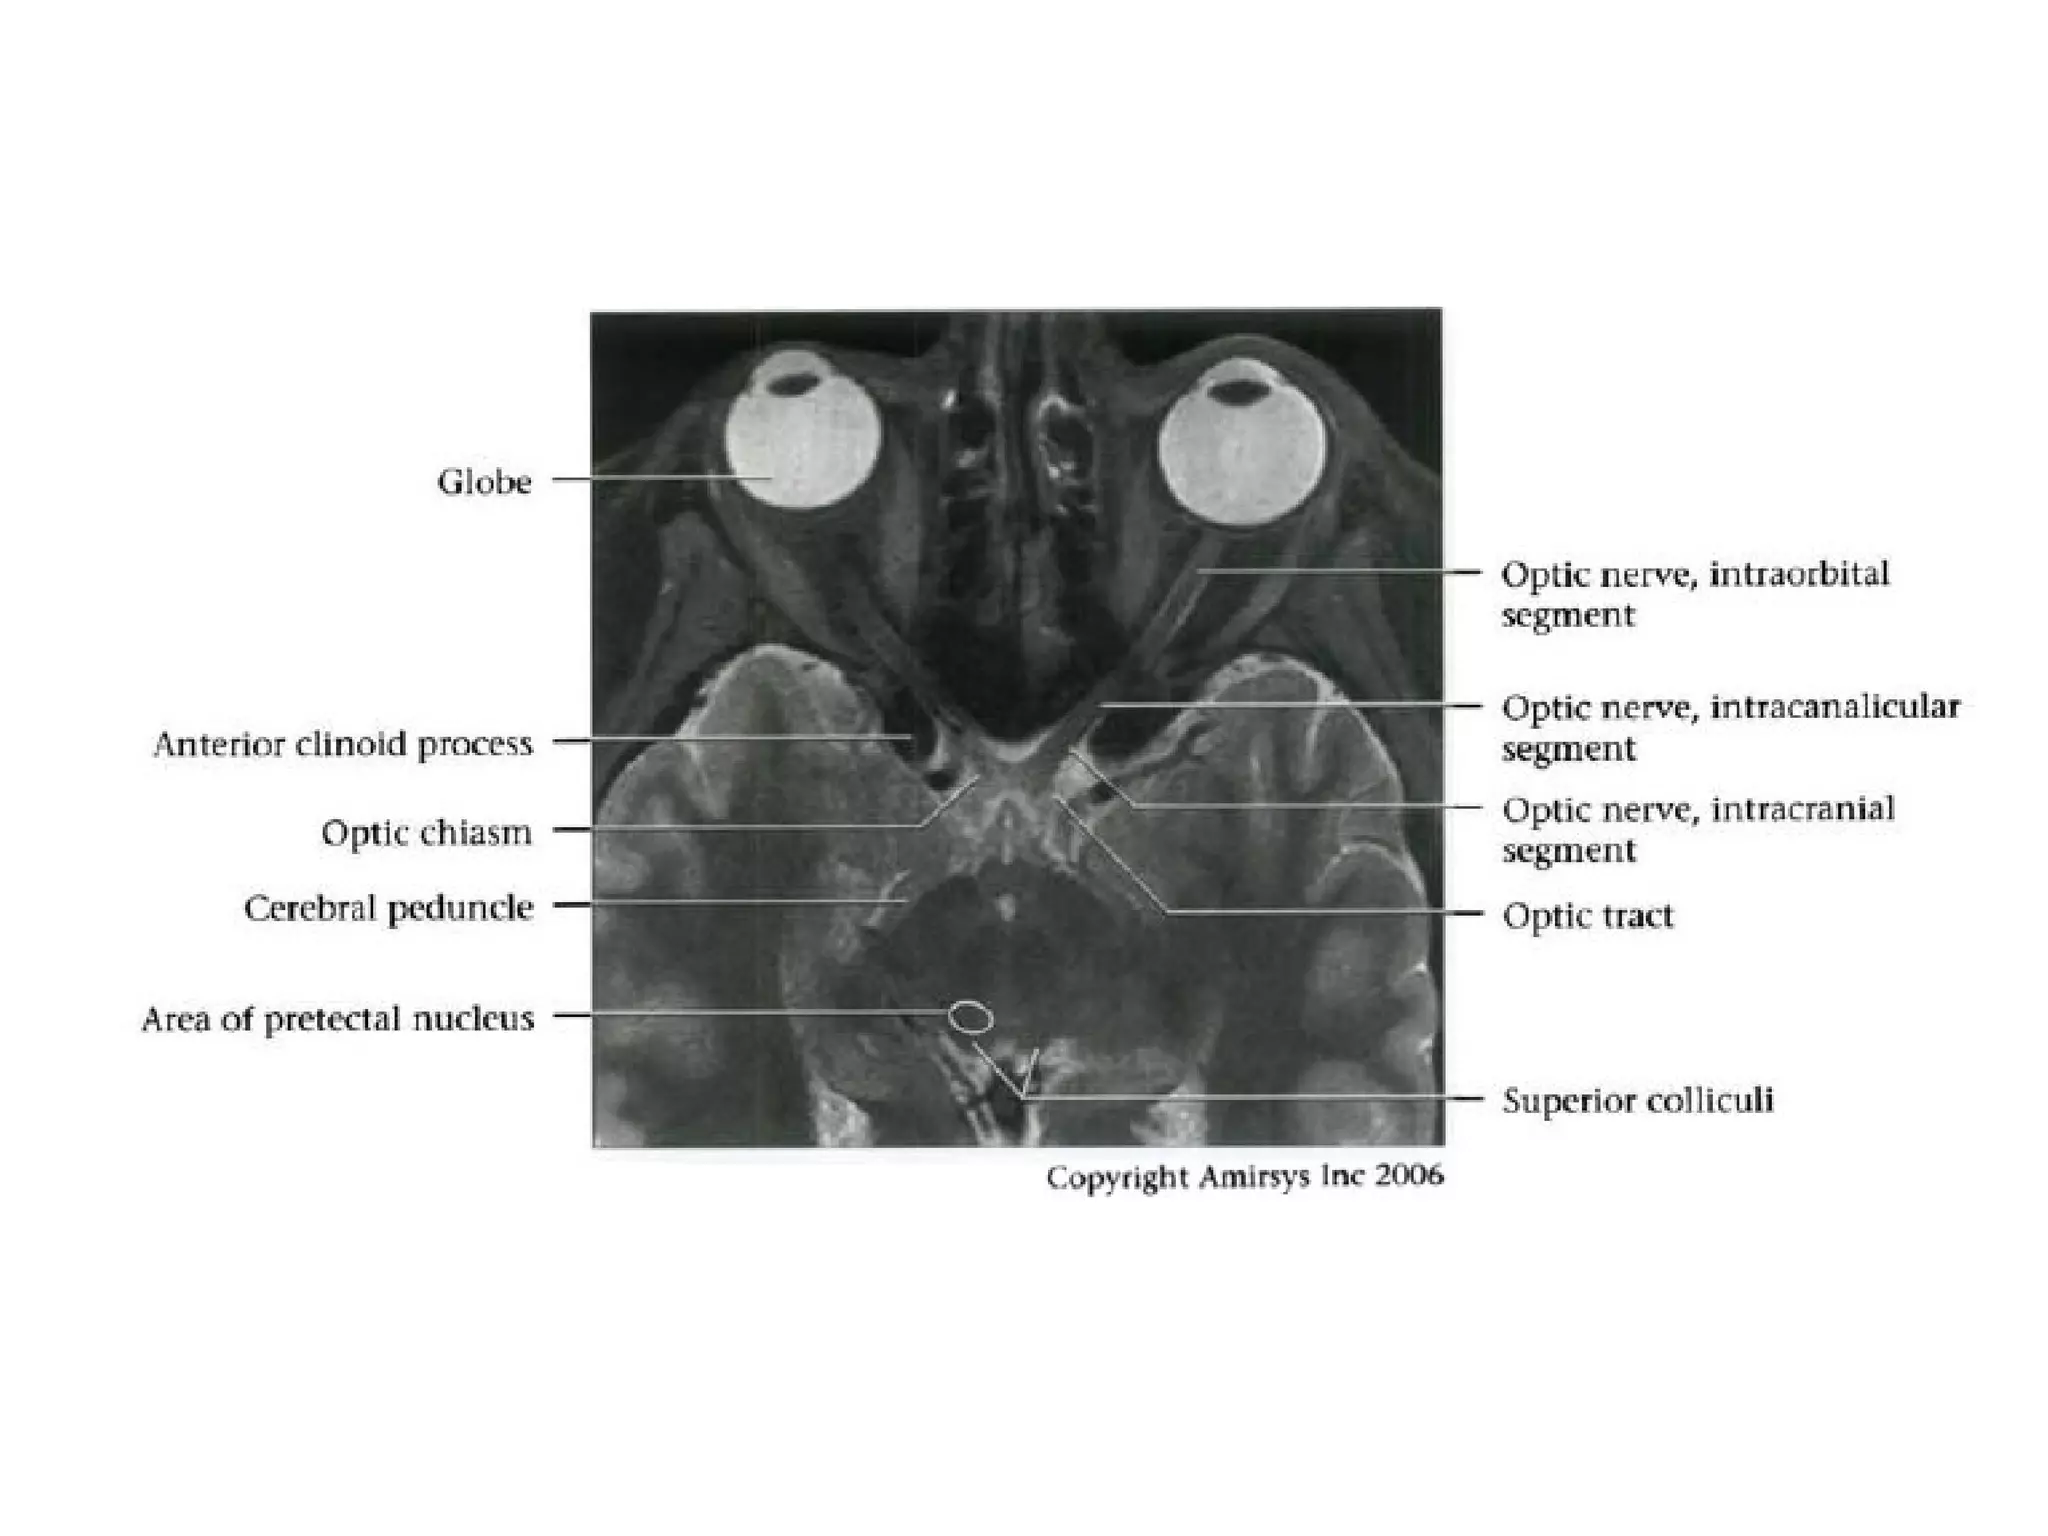

Cranial Nerve II:

The Optic Nerve

• Like the olfactory nerve, the optic nerve is a white-matter tract

without surrounding Schwann cells.

• It includes four anatomic segments: retinal, orbital, canalicular,

and cisternal.

• The retinal segment leaves the ocular globe through the lamina

cribrosa sclerae (the optic foramen of the sclera).

• The orbital segment, which is surrounded by a dural sheath

containing CSF, travels through the center of the fat-filled orbit.

• The canalicular segment is the portion that lies in the optic canal,

below the ophthalmic artery. This segment of the nerve is frequently

overlooked on radiologic images, so it should be specifically sought

when imaging for vision loss.

• Finally, the cisternal segment of the nerve can be visualized in the

suprasellar cistern, where the nerve leads to the optic chiasm. The

anterior cerebral artery passes over the superolateral aspect of the

cisternal segment of the nerve.

RadioGraphics 2009; 29:1045–1055

• Key anatomic landmarks in the suprasellar cistern

include the infundibulum (stalk) of the pituitary gland, the

anterior cerebral artery, and, posterior to the chiasm, the

mamillary bodies.

• The optic nerve terminates at the optic chiasm, where

the two nerves meet, decussate, and form the optic

tracts.

• The optic tracts travel around the cerebral peduncles,

after which most axons enter the lateral geniculate body

of the thalamus, loop around the inferior horns of the

lateral ventricles (Meyer loop), and enter the visual

cortex in the occipital lobe.

Optic nerve.

Axial oblique 0.8-mm-thick SSFP MR image shows three of four segments of the optic

nerve: the retinal (black arrow), orbital (black arrowheads), and canalicular (white

arrowhead) segments. The infundibulum of the pituitary gland (white arrow) also is

seen. The fourth (cisternal) segment of the optic nerve would be visible on more

superior images.

The cisternal segment of the optic nerve (white arrow) leads to the chiasm, which

resembles the Greek letter χ in this plane. The optic tract (white arrowheads) leads

backward from the chiasm to the thalamus. Important anatomic landmarks include the

mamillary bodies (black arrowhead) and the anterior cerebral artery (black arrow).